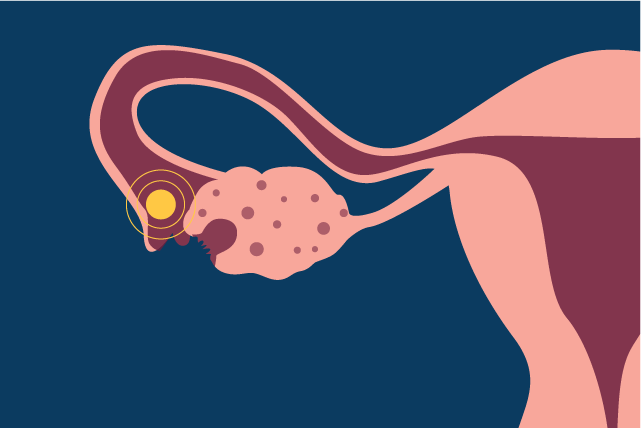

Beberapa wanita sering merasakan nyeri tumpul pada salah satu sisi perut bagian bawah. Sensasi ini muncul saat ovarium melepaskan sel telur untuk memulai perjalanan menuju saluran tuba. Selain nyeri perut, payudara juga cenderung terasa lebih sensitif atau sedikit kencang dari biasanya.